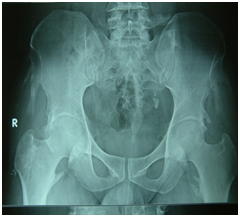

Figure 7 X ray pelvis: multiple soft tissue calcification- ligamental calcifications at different ligamental insertion sites. Left sided radio opacities (uretric calculi),No evidence of sacroilitis.